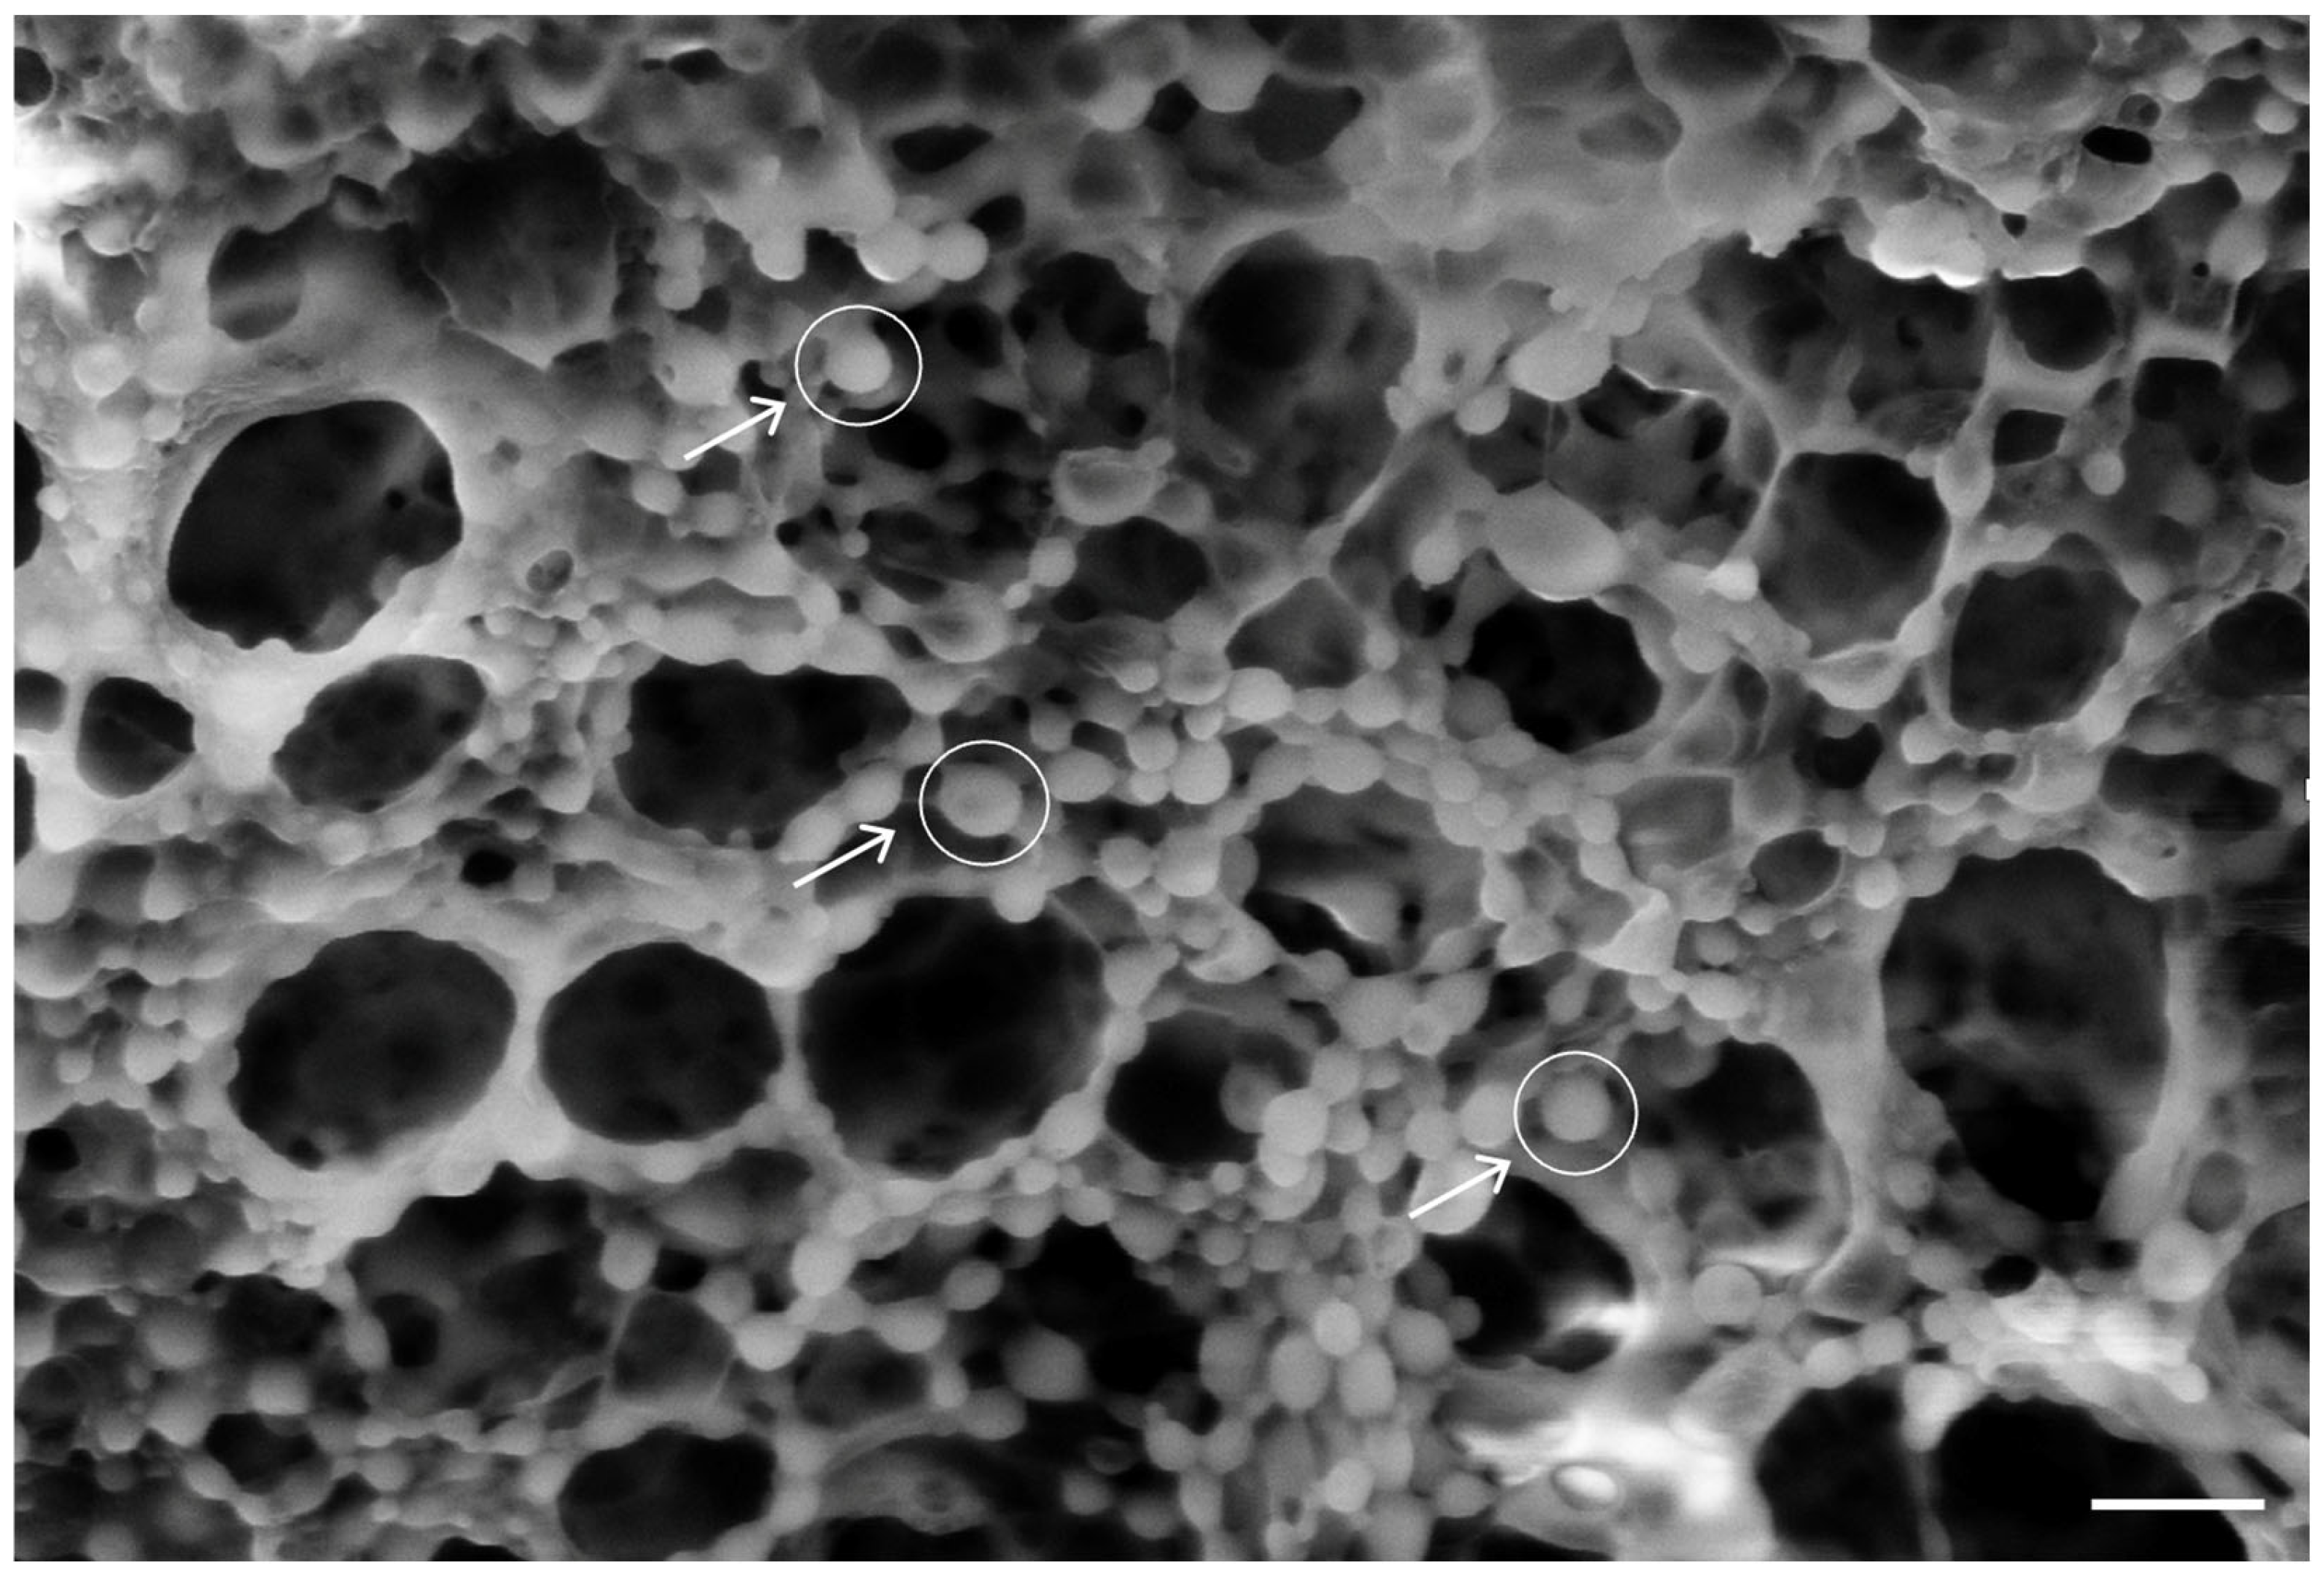

3.8. PLGA-NP Integration into PLA-FBs and Release in DMEM